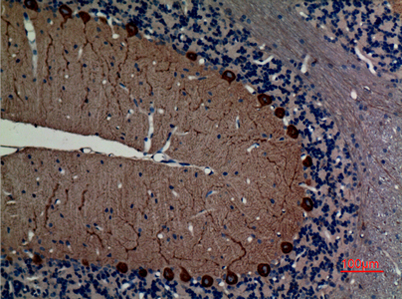

Product name: NF-L rabbit pAb

Dilutions: Western Blot: 1/500 - 1/2000. IHC-p: 1:100-300 ELISA: 1/40000. Not yet tested in other applications.

Immunogen: Synthesized peptide derived from the C-terminal region of human NF-L.

Cellular localization: Cell projection, axon . Cytoplasm, cytoskeleton .

Background: Neurofilaments are type IV intermediate filament heteropolymers composed of light, medium, and heavy chains. Neurofilaments comprise the axoskeleton and they functionally maintain the neuronal caliber. They may also play a role in intracellular transport to axons and dendrites. This gene encodes the light chain neurofilament protein. Mutations in this gene cause Charcot-Marie-Tooth disease types 1F (CMT1F) and 2E (CMT2E), disorders of the peripheral nervous system that are characterized by distinct neuropathies. A pseudogene has been identified on chromosome Y. [provided by RefSeq, Oct 2008],